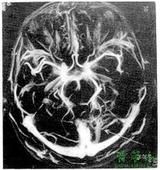

腦靜脈畸形血管造影近年來發展起來一種新的MRA方法,稱對比增強MRA,其適用範圍廣,實用性強,方法是靜脈內團注2~3倍於常規劑量的Gd-dtpa對比劑,採用超短TR、TE快速梯度回波技術,三維採集,該方法對胸腹部及四肢血管的顯示極其優越。

腦梗塞、腦腫瘤、炎症、變性病、先天畸形、外傷等,為套用最早的人體系統,目前積累了豐富的經驗,對病變的定位、定性診斷較為準確、及時,可發現早期病變。